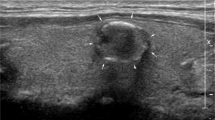

An artificial intelligence (AI) algorithm based on convolutional neural networks was used in ultrasound diagnosis in order to evaluate its performance in judging the nature of thyroid nodules and nodule classification.

A total of 105 patients with thyroid nodules confirmed by surgery or biopsy were retrospectively analyzed. The properties, characteristics, and classification of thyroid nodules were evaluated by sonographers and by AI to obtain combined diagnoses. Receiver operating characteristic curves were generated to evaluate the performance of AI, the sonographer, and their combined effort in diagnosing the nature of thyroid nodules and classifying their characteristics. In the diagnosis of thyroid nodules with solid components, hypoechoic appearance, indistinct borders, Anteroposterior/transverse diameter ratio > 1(A/T > 1), and calcification performed by sonographers and by AI, the properties exhibited statistically significant differences.